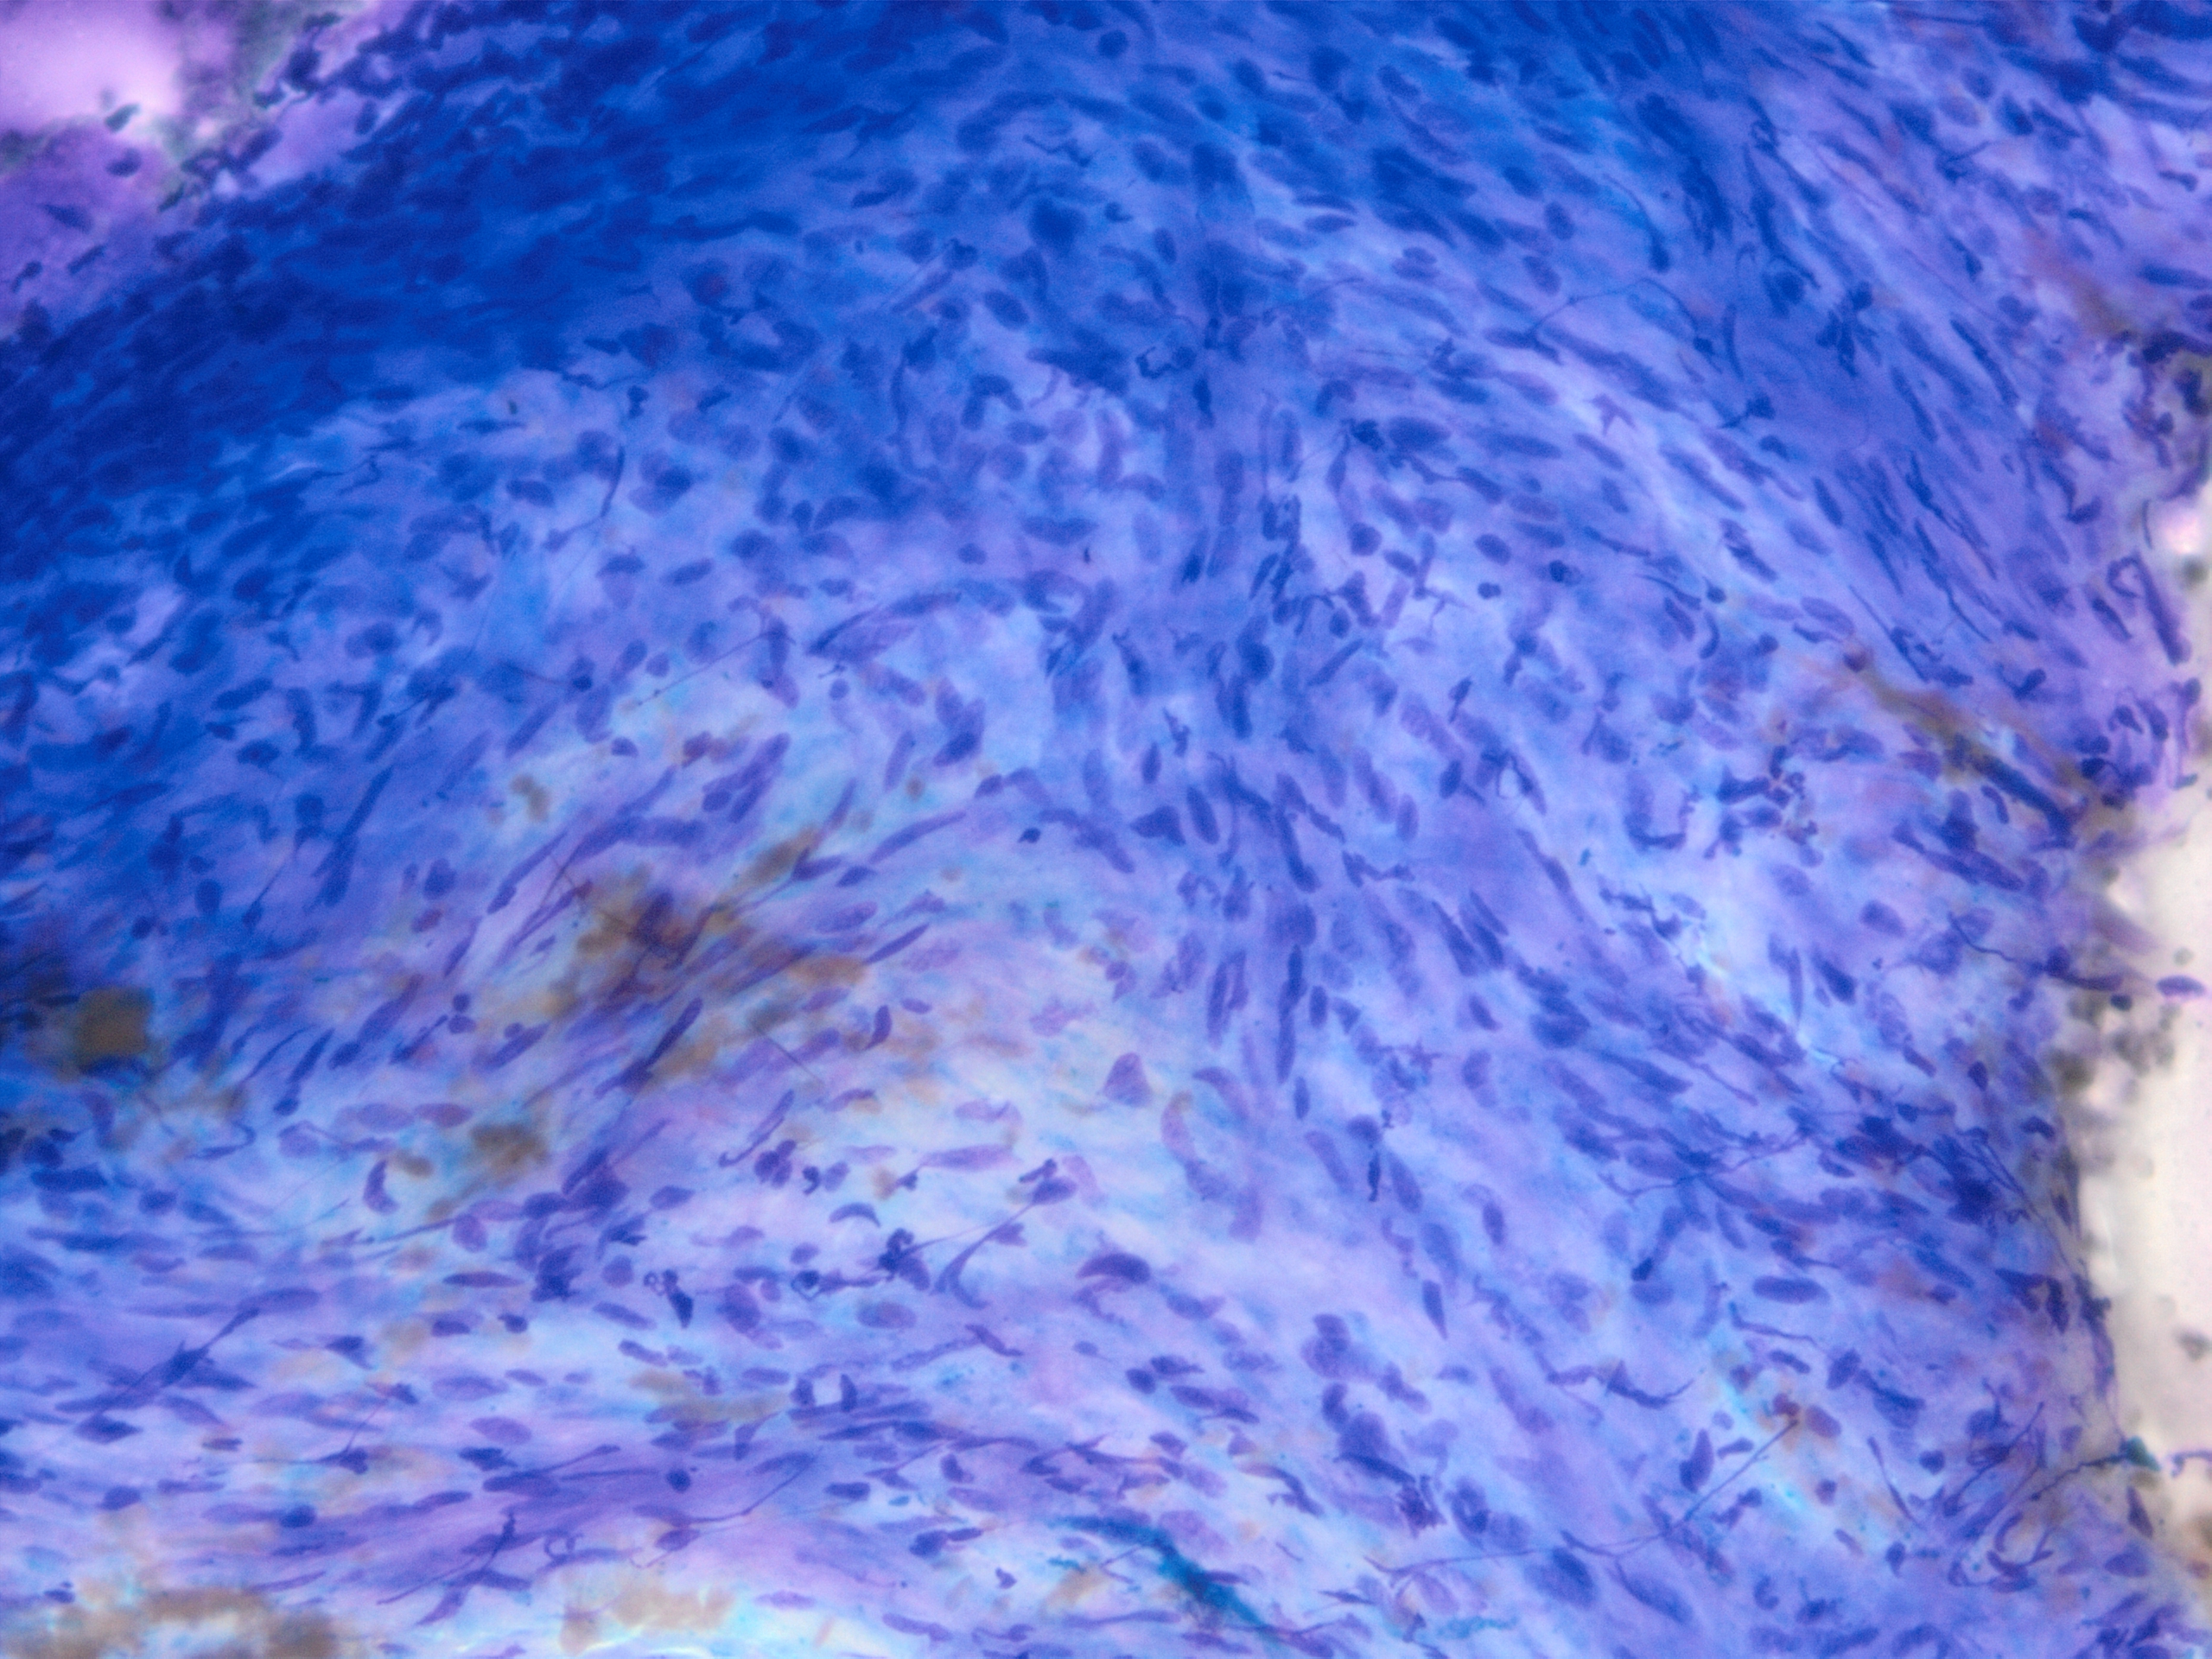

Immunohistochemistry was diffusely positive for Sox-10 and negative for C117 (C-kit), DOG1, SMA, CD34, supporting neural crest origin. On cytology, note a large tissue fragment with variable cellularity showing oval to wavy, “fishhook” nuclei on higher magnification and indistinct cell borders. On cell block, note the abundant filamentous cytoplasm and subtle nuclear palisading.